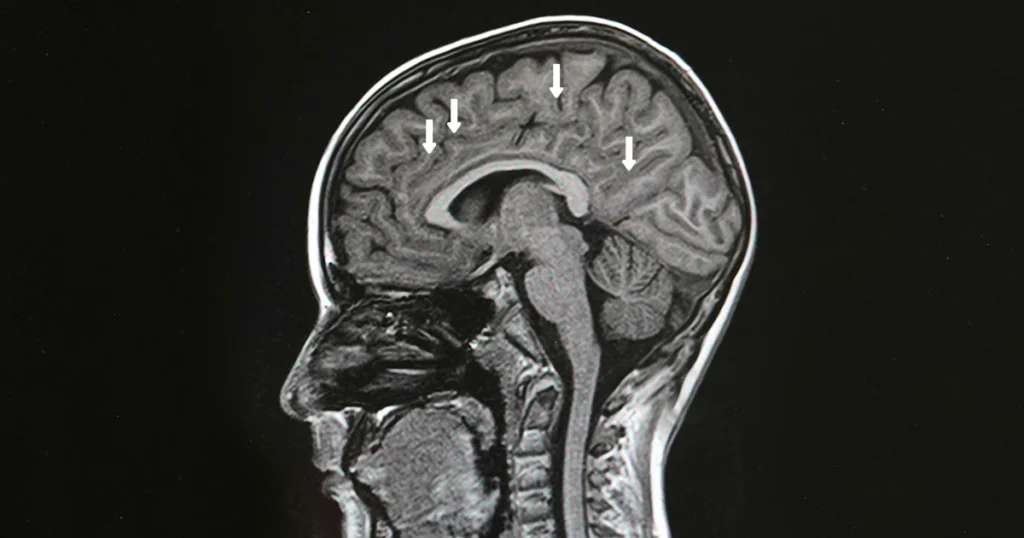

An MRI is one of the most important tools for diagnosing MS because it shows inflammation that isn’t always noticeable through physical exams. Neurologists pay close attention to brain lesions in multiple sclerosis, which often appear as bright spots on MRI scans. These lesions reflect areas where the immune system has damaged the protective coating around nerves.

Brain Lesions in Multiple Sclerosis

Brain lesions are a key marker of MS because they show areas where the immune system has damaged the myelin, the protective coating around nerve fibers. These lesions can appear in several regions, including the periventricular area, cerebellum, brainstem, and spinal cord. Their location often explains symptoms like numbness, poor coordination, or vision issues.

Understanding lesion activity helps neurologists determine how active the disease is. Over time, changes in lesion size or number can reveal whether treatments are slowing inflammation or if another medication may be necessary.